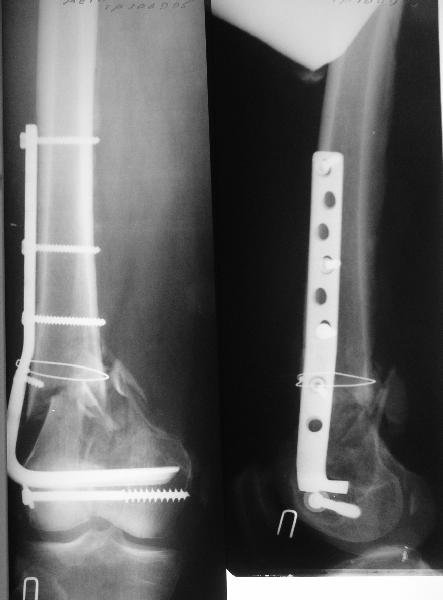

Длину восстановили, возможно, даже с изьбытком, ну да динамизируем пораньше. Введенные в овальное отверстие дистальые винты имеют угловую стабильность. Снимки приложены. Заранее спасибо за критику и комментарии.

Довольно симпатично получилось. Не сомневался, что будет именно такой антеградный реостеосинтез.

Была ли педресация на столе после окончательной фиксации? Уверен ли ты, что "угловая стабильность" дистальных винтов позволит агрессивно заниматься разработкой движений в коленном суставе?

Comments:

This is a worst site for non-union.

Bone grafting could have been done at reoperation.

Nicely executed surgery with good planning resulting in great looking x-rays but not the best the way to deal with this fracture. Earlier fracture was having slight translation with no angulation and no instability, now ur fracture is distracted with potential instability as your construct is not the best suited to this place, so more likelihood of non union or complications.

Good luck to you and your patient

Should have preferred a locking plate if at all u wanted to reoperate and

added copious bone graft.